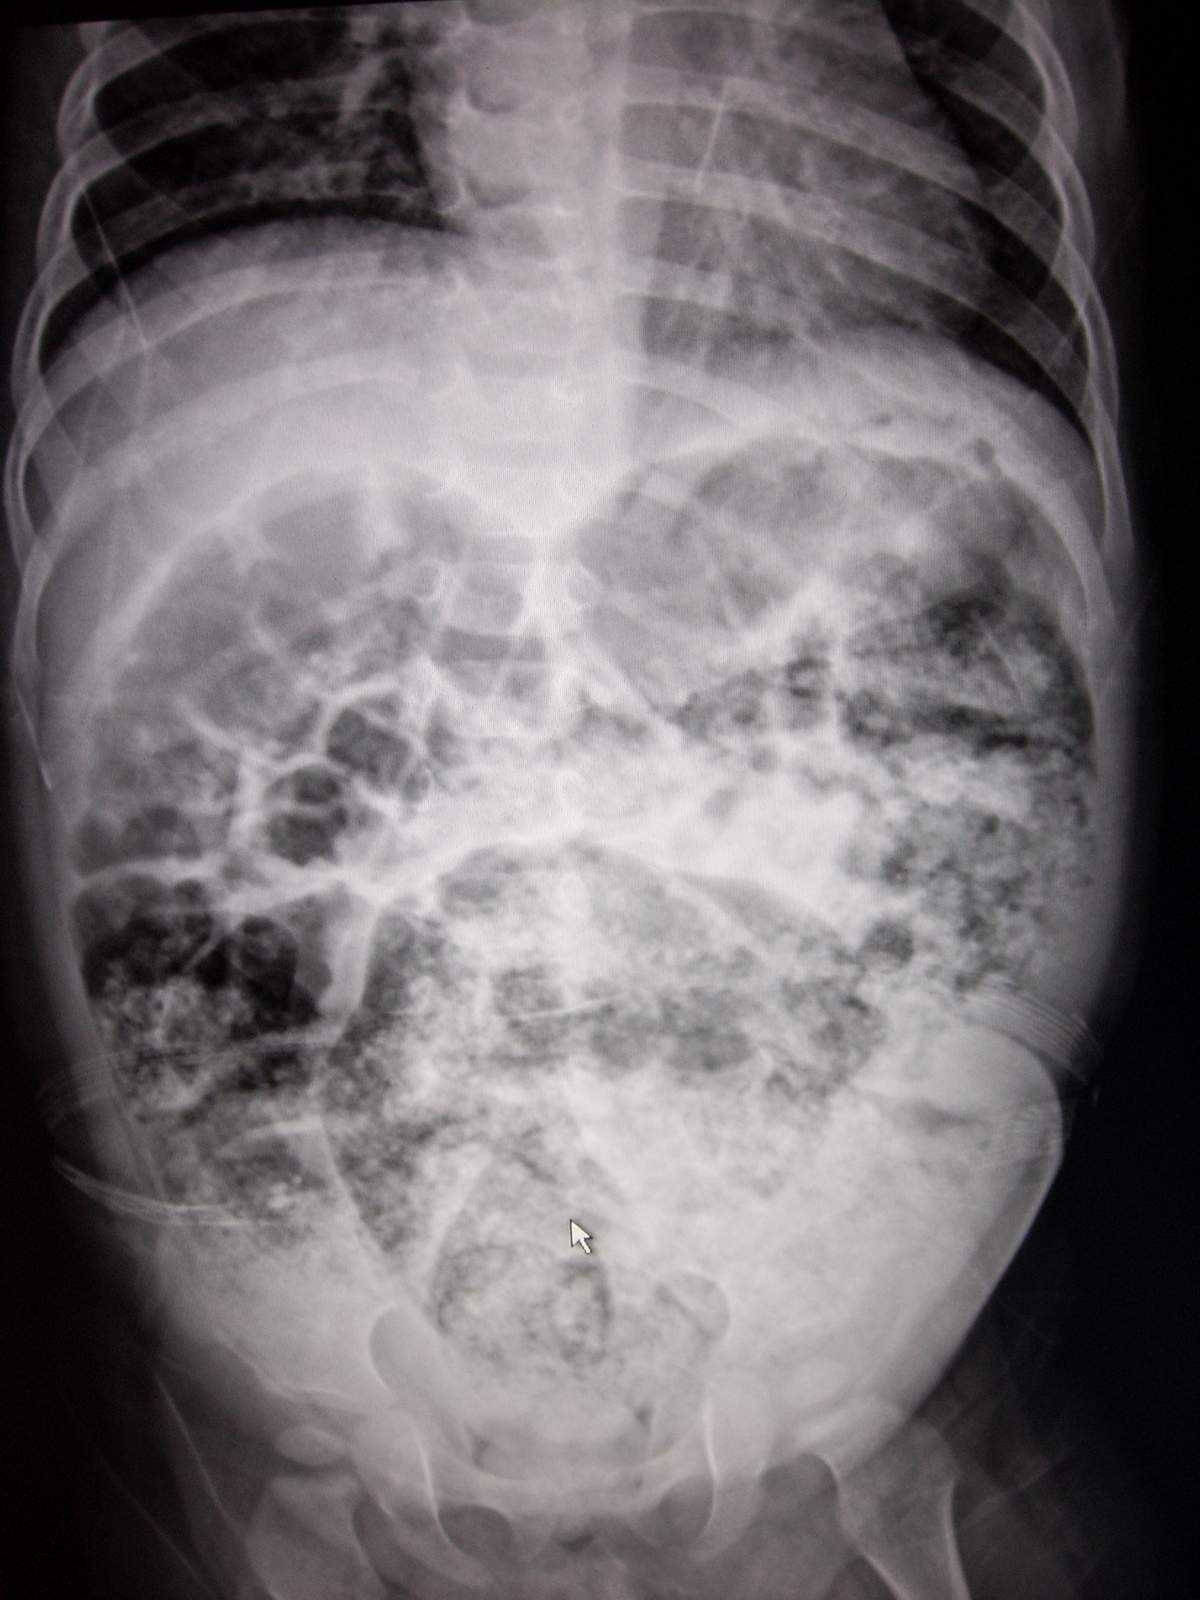

女,11月,腹胀2天,腹膨隆,肌软,肠鸣音存在。

腹部见大量粪便,可考虑先天性巨结肠。建议加照立位或钡灌肠。

升结肠.横结肠.降结肠中.上段及乙状结肠积气扩张,降结肠下段局限性狭窄.考虑先天性巨结肠.

考虑粪石梗阻性结肠扩张,11月,腹胀2天,巨结肠临床好像不太支持。